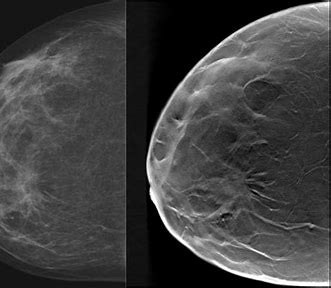

What is a 3D Mammography?

Breast tomosynthesis allows doctors to examine breast tissue one layer at a time. Breast tomosynthesis is a new technology in the fight against breast cancer. Breast tomosynthesis may be used in conjunction with traditional digital mammography as part of your annual screening mammogram to capture more breast images. Very low X-ray energy is used during the screening examination so your radiation exposure is safely below the American College of Radiology (ACR) guidelines. Using breast tomosysnthesis and digital mammography together for screening has been proven to reduce “call backs”.

Breast tomosynthesis may be used for a diagnostic mammogram if you happen to need one.

More accurate detection: By minimizing the impact of overlapping breast tissue, 3D mammography can make a tumor easier to see. Reviewing multiple images has helped doctors find more cancers than with 2D images alone.